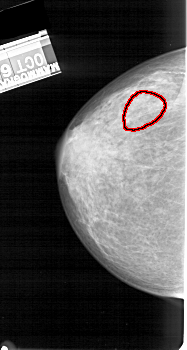

FILE: A_1393_1.LEFT_MLO.OVERLAY

TOTAL_ABNORMALITIES 1

ABNORMALITY 1

LESION_TYPE CALCIFICATION TYPE AMORPHOUS DISTRIBUTION SEGMENTAL

ASSESSMENT 4

SUBTLETY 2

PATHOLOGY BENIGN

TOTAL_OUTLINES 1

BOUNDARY